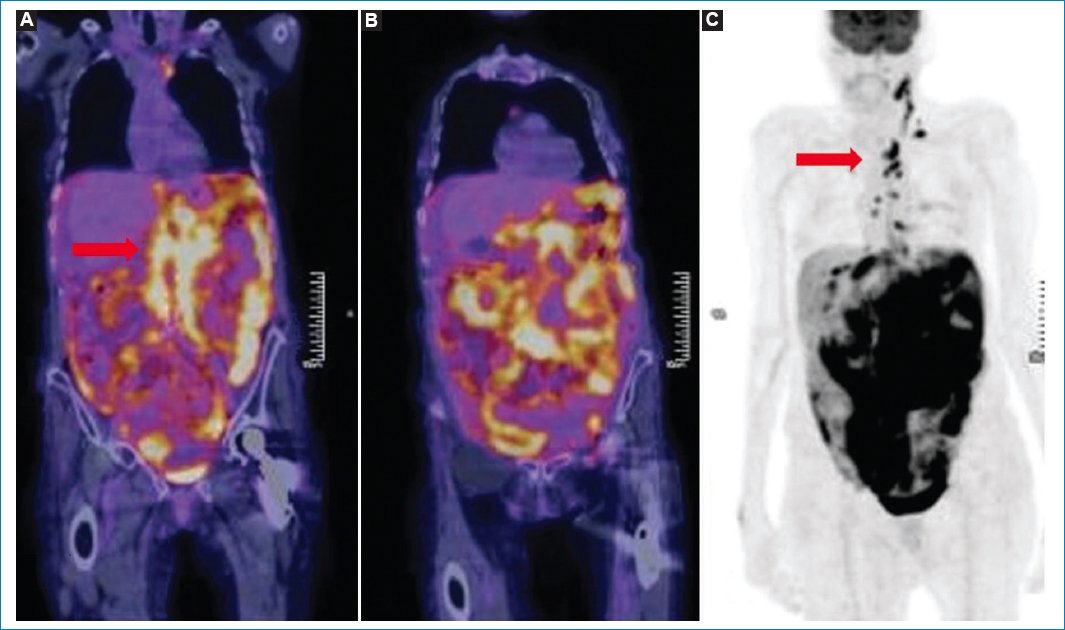

Según Cabral et al.11, el patrón más frecuente de presentación de la LP consiste en la observación del omental cake hipermetabólico, con conglomerados ganglionares múltiples (Fig. 15). El compromiso peritoneal aislado, sin afectación ganglionar, es extremadamente inusual33.

Figura 15. Patrón más frecuente de presentación de la LP, con compromiso difuso peritoneal hipermetabólico (omental cake, flecha) y adenomegalias múltiples; hallazgos evidentes en las imágenes de fusión PET-TC en sagital (A) y coronal (B).